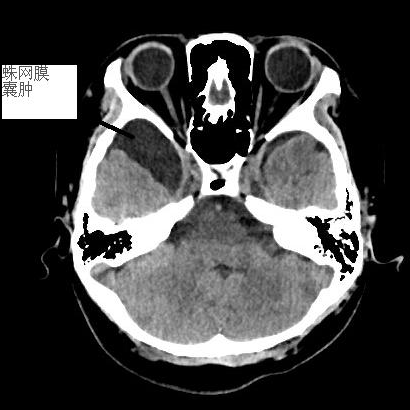

近日,我院接診一位小朋友,因頭部磕碰后感覺頭痛由家屬護(hù)送到急診科就診。經(jīng)查CT,未見明顯外傷征象,報(bào)告提示為右顳葉蛛網(wǎng)膜囊腫。我院神經(jīng)外科謝醫(yī)生告知檢查結(jié)果后,家長(zhǎng)很緊張。謝醫(yī)生耐心詢問(wèn)病史,了解到小朋友平時(shí)無(wú)明顯頭部不適且生長(zhǎng)發(fā)育正常,考慮到蛛網(wǎng)膜囊腫占位效應(yīng)不明顯,暫予觀察,囑隨診復(fù)查。

顱內(nèi)蛛網(wǎng)膜囊腫是顱內(nèi)蛛網(wǎng)膜形成的、內(nèi)含腦脊液的、非腫瘤性、囊性病變。囊壁為一層纖維結(jié)締組織,壁內(nèi)附一層扁平蛛網(wǎng)膜細(xì)胞;囊液成分多同腦脊液,蛋白增高者可呈淡黃色;囊腫可呈多房性。因囊腫發(fā)生部位不同而形態(tài)各異,可伴有局部腦組織的受壓萎縮,局部骨瓣(顳、枕骨鱗部)受壓變薄并向外膨隆,還可伴有先天性顳葉發(fā)育不全。顱內(nèi)蛛網(wǎng)膜囊腫多為先天性,男女比例為4∶1。部位以外側(cè)裂和顳前部多見,其次為枕大池、大腦凸面,再次為四疊體池、鞍區(qū)、腦室內(nèi)、橋小腦角和大腦縱裂。